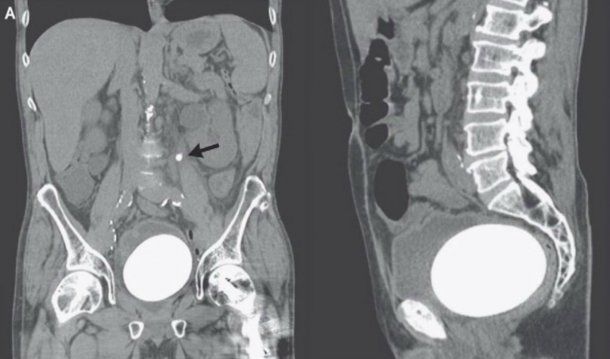

Medios07/09/2017Un hombre de California, en los Estados Unidos, fue al médico por un dolor constante en la zona baja del abdomen y problemas para orinar y los médicos descubrieron que tenía una piedra de 770 gramos alojada en la vejiga.

La mayoría de las piedras que se forman en el riñón o la vejiga son tan pequeñas que el cuerpo las puede expulsar por las vías naturales -aunque sea con un poco de dolor- pero en el caso de este paciente de 64 años el bulto tenía el tamaño y la forma de un huevo de avestruz, informó el sitio Daily Mail.